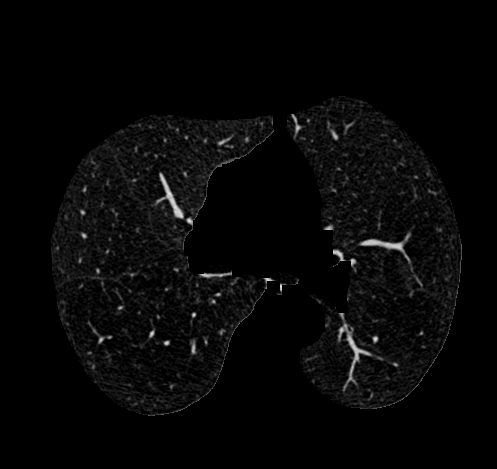

2.计算位于肺周围区域的平均像素值,并将被遮挡或损坏的图像进行重新归一化处理。通过K-means算法分别识别出目标物体(不透明组织)与背景区域(透明组织),其中背景区域重点关注的是肺部区域。这种处理方法仅针对图像中心区域实施,并尽力避免对未参与区域产生影响

- 采用腐蚀与膨胀的操作进行处理。如需了解详细内容可参考https://www.jianshu.com/p/05ef50ac89ac。腐蚀操作能够有效去除某些区域的颗粒状结构;随后采用较大的膨胀作用于肺部血管及其周围组织,并以消除血管周围的黑色噪声为主,在此过程中尤其是由于不透明射线导致的肺部阴影区域也会得到适当的清理与处理。

- 获取肺部掩膜。选择CT图像中心区域的目的在于去除周围非感兴趣区域(如床板等),随后对图像进行连通域分析并确定较大的连通域作为肺部掩膜基础。在此基础上实施一次较大范围的膨胀操作用于填充和提取肺部掩膜区域。**此时边界可能出现不规则现象:可以通过腐蚀操作优化边界细节;然而需要注意的是,在此步骤之前已经进行了充分的大范围膨胀操作;因此可能会导致内部空洞扩大风险(因为后续的腐蚀处理可能进一步放大原有空洞)。